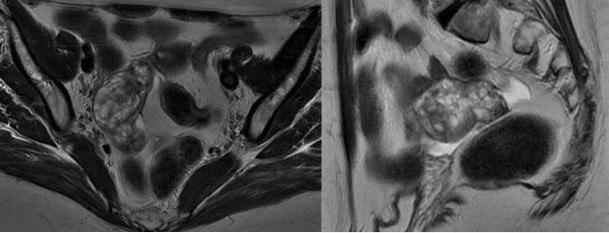

Paciente femenina de 56 años de edad, que durante evaluación ginecológica se evidencia por ultrasonido lesión en ovario derecho ecomixta de 5,5 cm x 4,9 cm, solicitándose marcadores tumorales (CA-125, CEA y CA15-3) los cuales se reportan normales y RMN abdomino-pélvica confirmando la presencia de lesión ocupante a nivel de anexo derecho, heterogénea de predominio quístico que mide 6 cm x 3,3 cm asociado a dilatación de la trompa uterina ipsilateral con presencia de componente sólido en su interior (Figura 1); siendo llevada a mesa operatoria el 01/07/22 para histerectomía abdominal total con ooforectomía bilateral y en cuya biopsia peri-operatoria se informa tumor de células redondas por lo que se toma muestra de lavado de cavidad abdominal y se evalúa resto de órganos de la cavidad, sin signos de infiltración tumoral y culminando el acto operatorio sin complicaciones.